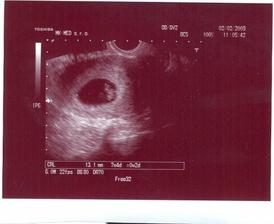

Ďalšie sono máme 2.2. 2009. Sono už máme za sebou. Bábo je 13,1 mm veľké. Dostali sme tehotenskú knižku a poslali nás na rôzne vyšetrenia. Od EKG po rôzne odbery a utz...